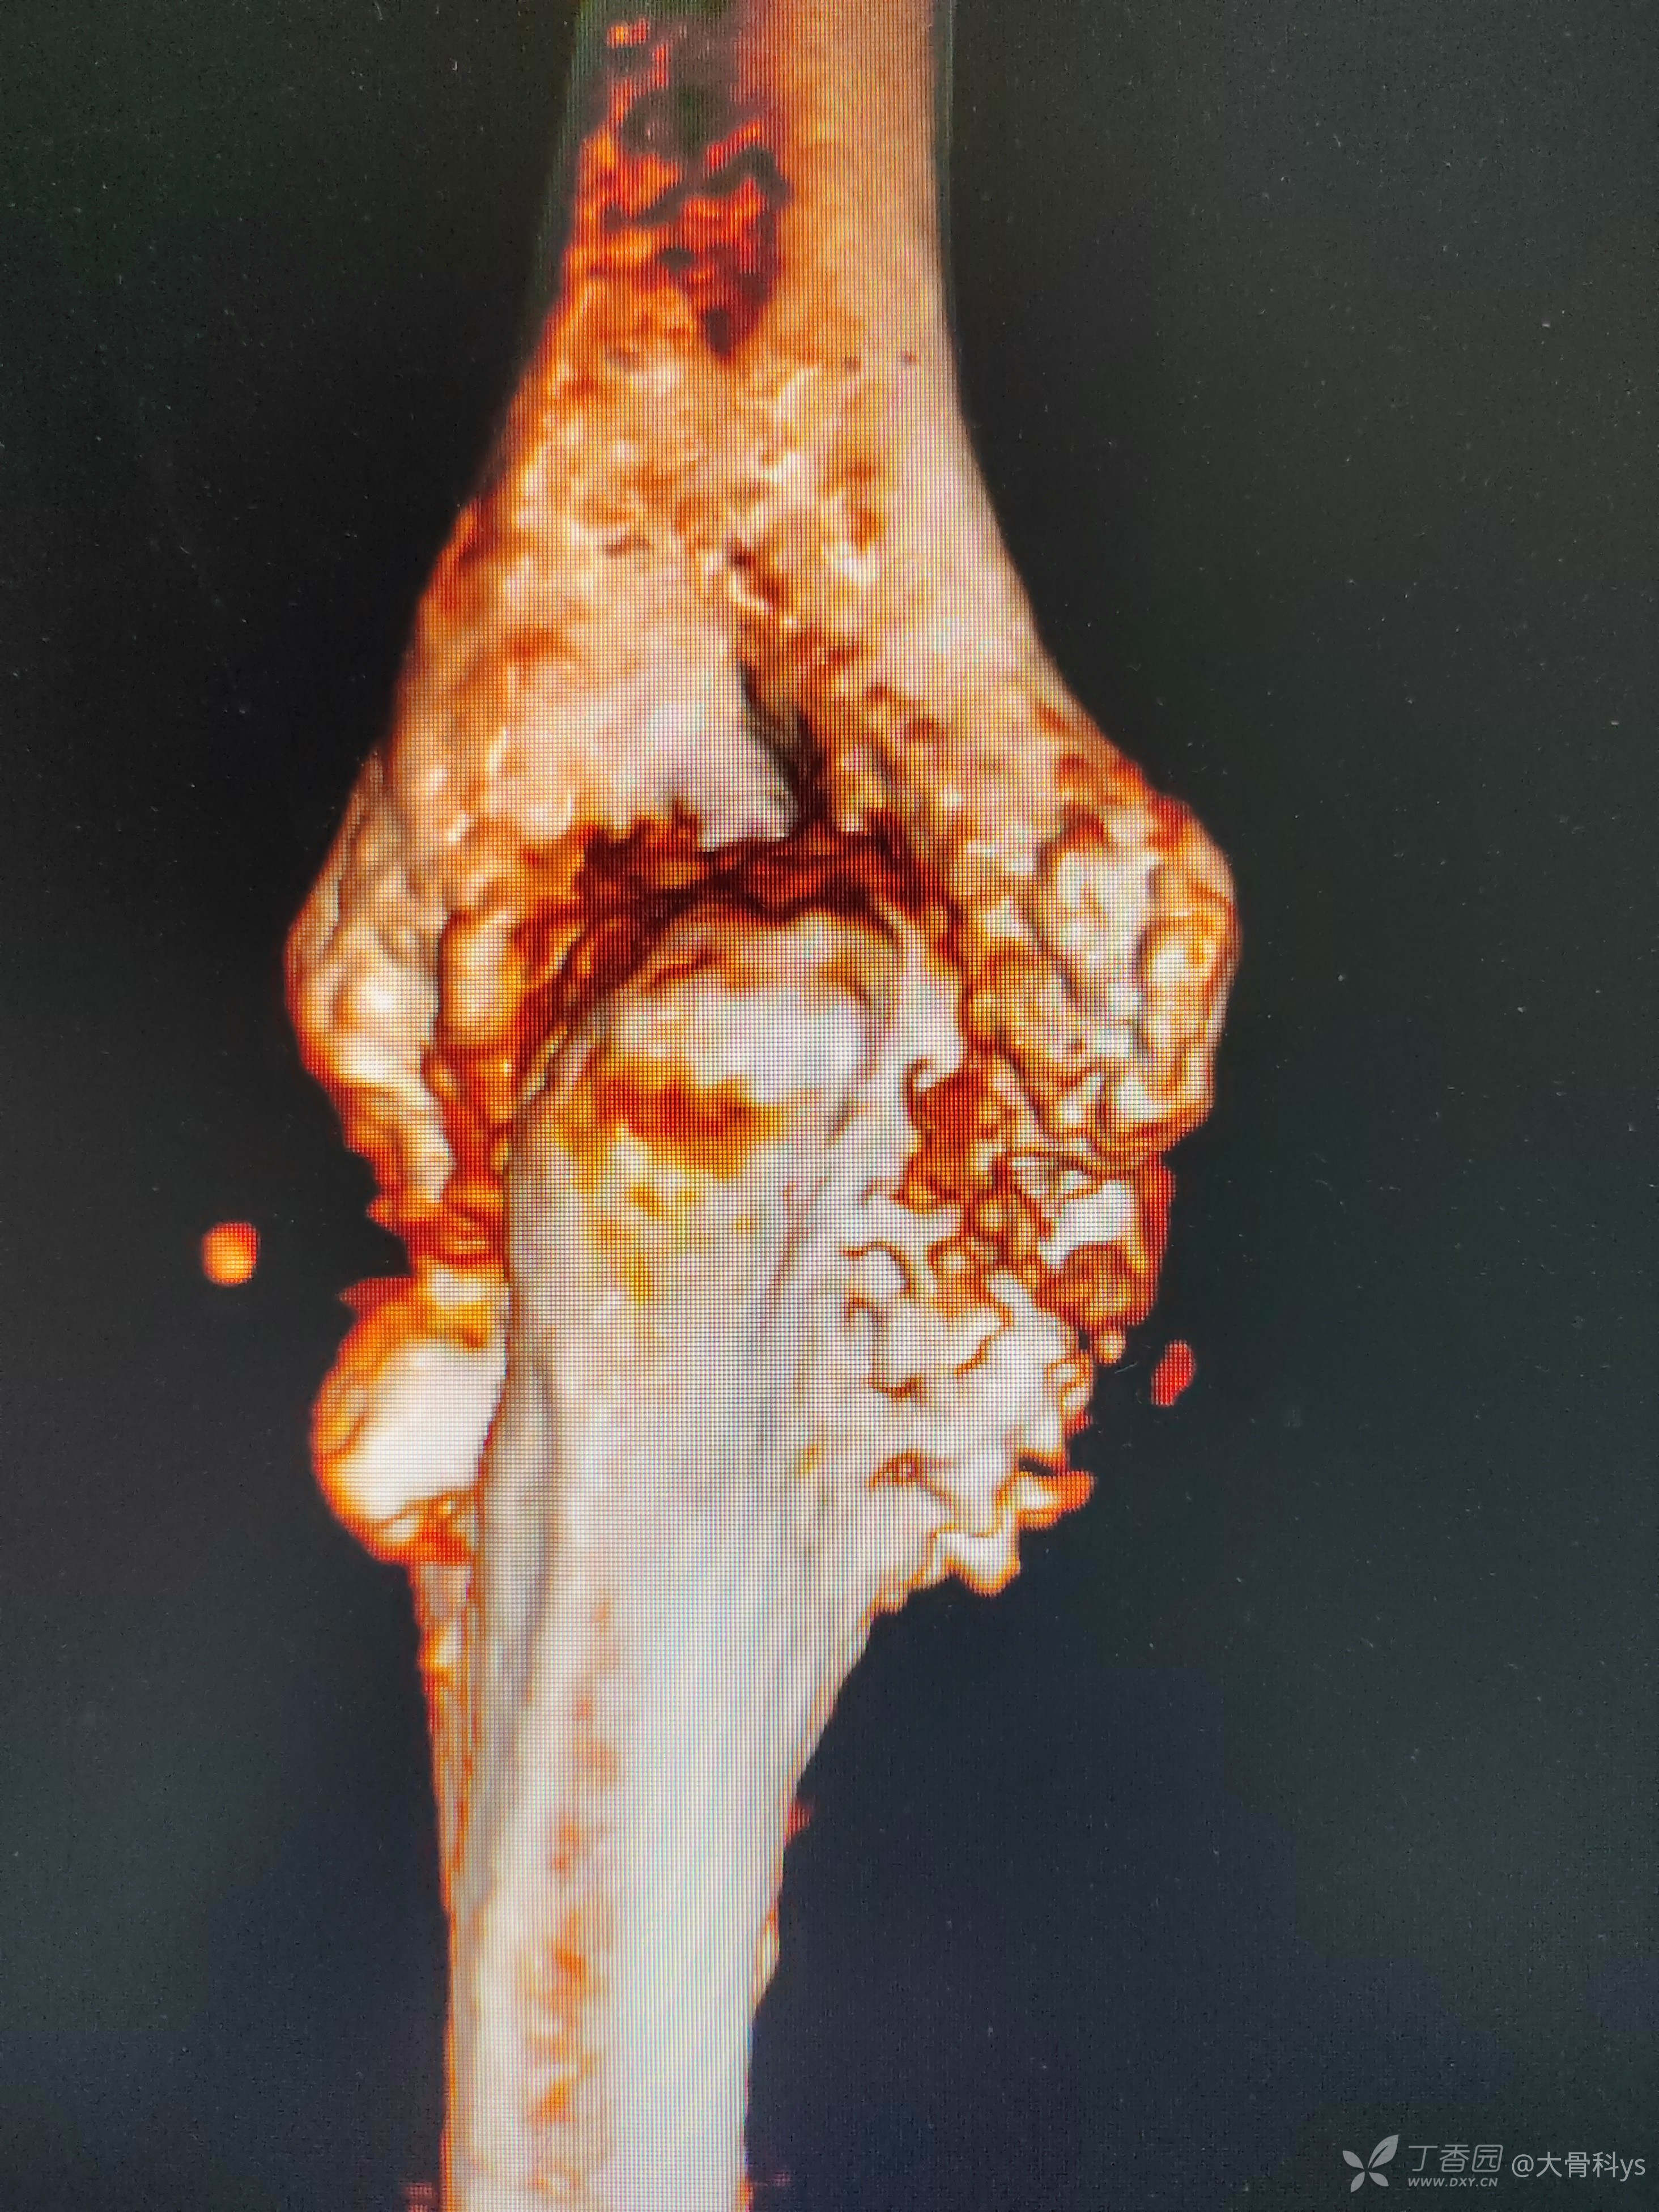

影像学资料

双肺CT检查提示双肺广泛性弥漫性改变:结核?尘肺?

考虑肘关节结核,行关节腔清理+骨髓炎病灶清除+负压封闭引流术。病灶组织再次培养,病灶组织结核杆菌培养,找抗酸杆菌,结核杆菌核酸及利福平耐药检测结果暂未回报。